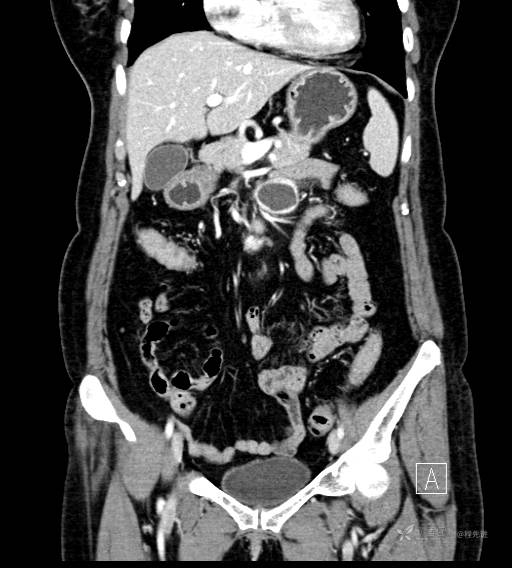

CT增强门脉期